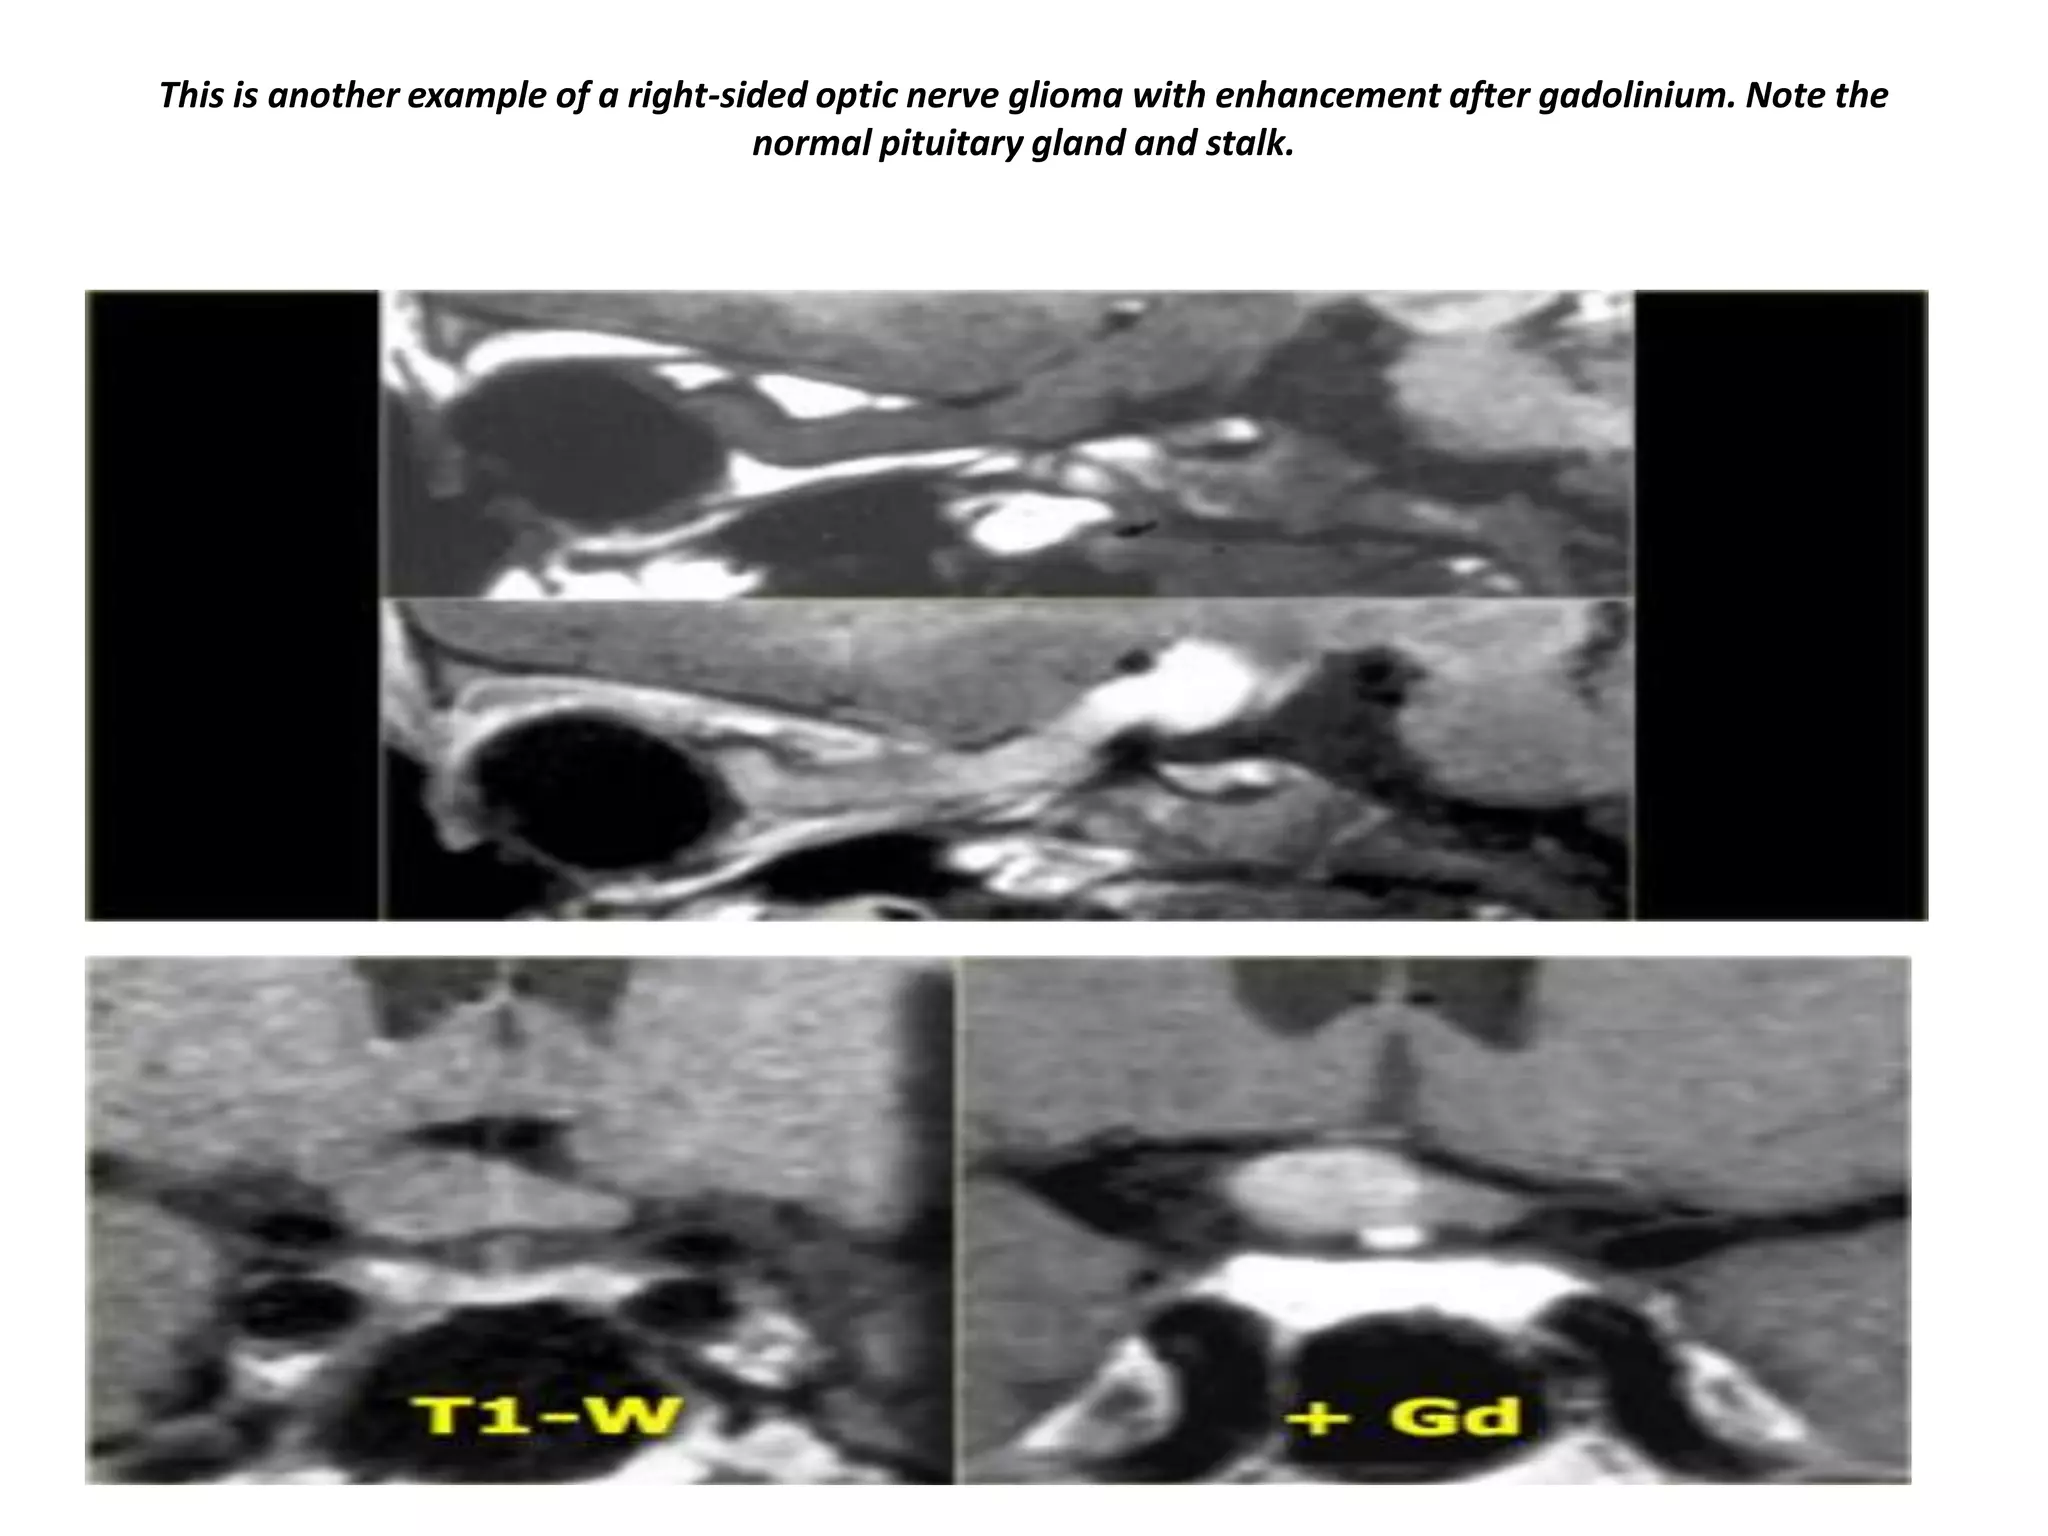

This is another example of a right-sided optic nerve glioma with enhancement after gadolinium. Note the

normal pituitary gland and stalk.